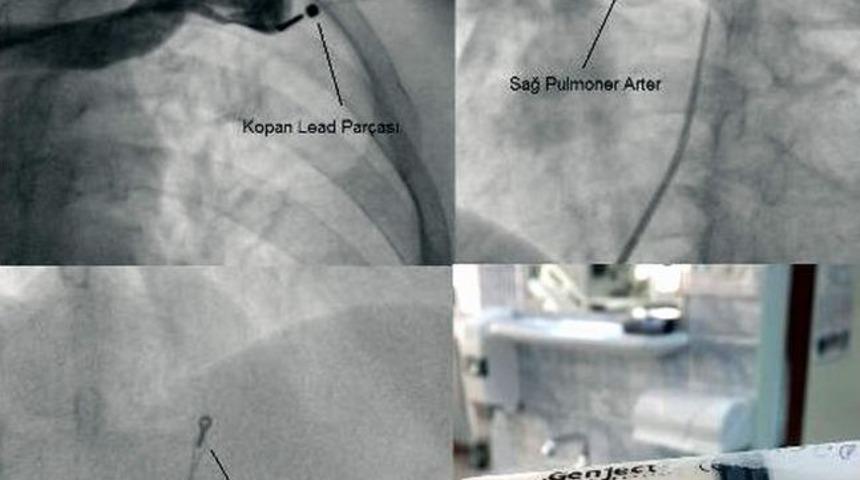

Adnan Menderes Üniversitesi (ADÜ) Uygulama ve Araştırma Hastanesi Kardiyoloji Kliniği, Aydın’da bir ilki gerçekleştirerek iki hastayı sağlığına kavuşturdu.Adnan Menderes Üniversitesi Uygulama ve Araştırma Hastanesi Kardiyoloji Kliniği, başarılı adımlarına iki basamak birden ekledi. ADÜ Uygulama ve Araştırma Hastanesi Kardiyoloji Kliniği’nde Yrd. Doç. Dr. Cemil Zencir, Yrd. Doç. Dr. Çağdaş Akgüllü ve Yrd. Doç. Dr. Ufuk Eryılmaz’dan oluşan ekip tarafından hastalardan birine kalıcı kalp pili ve lead çıkarma işlemi, diğerine ise sol kol atardamar proksimalinde gelişen ciddi darlığa balon ile dilatasyon yapıldıktan sonra balon expandaple stent yerleştirme işlemi Aydın’da ilk kez başarıyla gerçekleştirildi. Hastalar, işlemden bir gün sonra şifayla taburcu edildi.Yrd. Doç. Dr. Cemil Zencir, periferik atardamar hastalıklarının toplumda koroner kalp hastalığı, sigara içen ve şeker hastalığı olanlarda daha sık görüldüğünü, periferik atardamar hastalıklarının daha çok bacağa giden atar damarlarda gözlendiğini nadiren de kola giden atardamarda ortaya vurgulayarak balon ile dilatasyon yapılan hastanın, hastalığı ve tedavisi hakkında bilgi verdi. Dr. Zencir; “Bu tip hastalar, genellikle hareketle ortaya çıkan, dinlenmekle azalan ekstremite ağrıları sebebiyle doktora başvururlar. Bu hastalık, zamanında tedavi edilmediğinde ekstremitelerde morarma, kıl dökülmesi, yara, parmaklarda beslenme bozukluğu ve en sonunda ekstremite kesilmesini gerektirecek boyutta ciddi rahatsızlıklara yol açabilir. Periferik atar damarlarında ciddi darlık saptanan hastaların büyük bir kısmı ameliyata gerek kalmadan anjiyografi ile lokal anestezi (uyutulmadan) ile balon ve/veya stent ile tedavi edilebilmektedir” dedi.Kalıcı kalp pilinin leadi çıkarılması işleminin çok zor bir girişim olduğunu belirten Yrd. Doç. Dr. Cemil Zencir; “Hastamızda ilk seansta kalıcı kalp pili ve leadin büyük bir kısmının çıkarıldı sonraki seansta ise kopan küçük parçasının sağ pulmoner arterden snare ile yakalandıktan sonra ameliyata gerek kalmadan tamamen çıkarıldı” diye konuştu.Kardiyoloji kliniği olarak Aydın halkına hizmet vermekten gurur duyduklarını belirten Yrd.Doç.Dr. Cemil Zencir, “ Bu hizmeti bir ekip olarak gerçekleştiriyoruz, bize destek veren hocalarımıza, başhekimliğimize, asistanlarımıza ve yardımcı sağlık personelimize teşekkür ederiz” şeklinde konuştu.